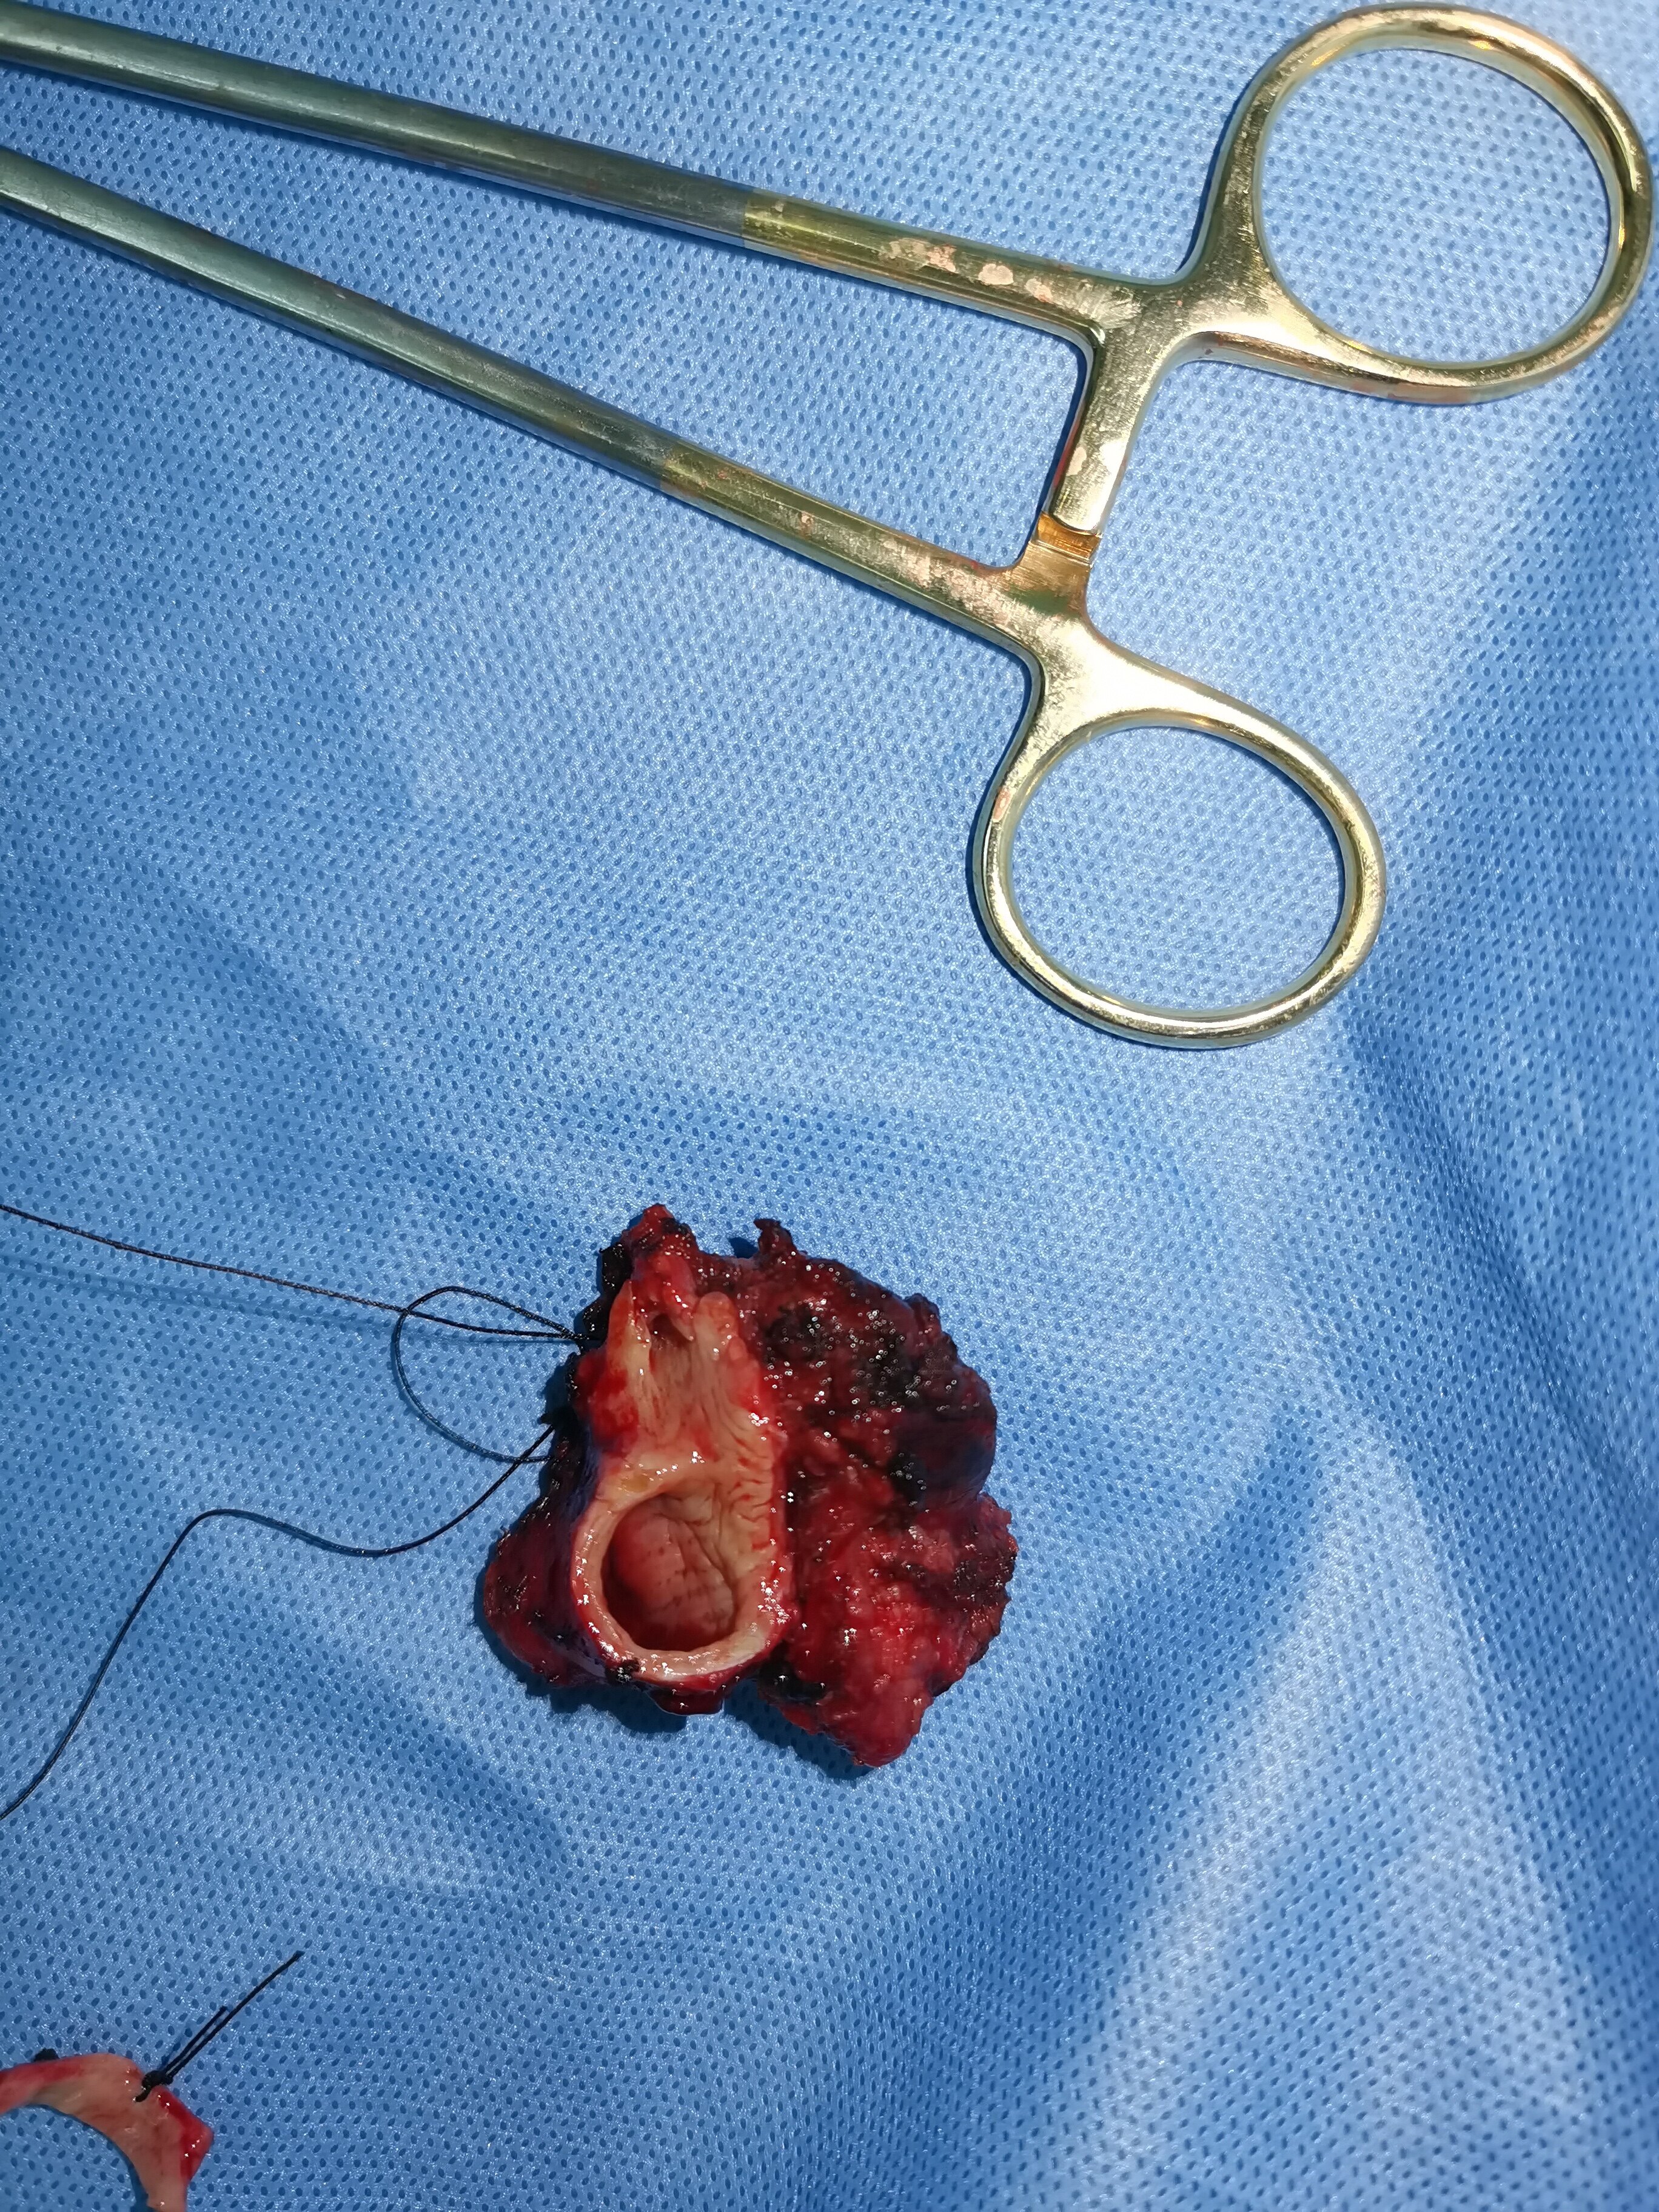

当肿瘤巨大,侵犯主要气管或者侵犯大血管时,并非一定不可以手术,而是可以通过心包内处理血管,这样更加安全避免血管大出血,侵犯气管主干是可以通过气管切除后,再行健康支气管修剪后原位移植,可以保留健康肺组织,避免全肺切除带来的风险和损失。这是我科最近手术的一例典型病例,肿瘤巨大且侵犯主气管,经过切除后原位移植,术后一周后复查CT,移植右上肺愈合良好,患者顺利康复出院